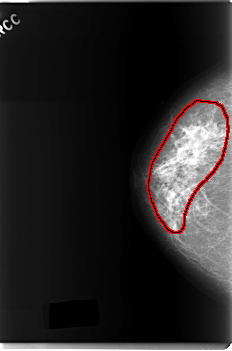

FILE: C_0179_1.RIGHT_CC.OVERLAY

TOTAL_ABNORMALITIES 1

ABNORMALITY 1

LESION_TYPE CALCIFICATION TYPE PLEOMORPHIC DISTRIBUTION REGIONAL

LESION_TYPE MASS SHAPE IRREGULAR MARGINS ILL_DEFINED

ASSESSMENT 5

SUBTLETY 5

PATHOLOGY MALIGNANT

TOTAL_OUTLINES 1

BOUNDARY

C_0179_1.RIGHT_CC

RIGHT_CC LINES 5960 PIXELS_PER_LINE 3928 BITS_PER_PIXEL 12 RESOLUTION 50 OVERLAY